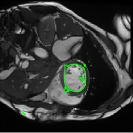

4.3 Comparison with cardic MR images for right ventricle segmentation

Cardiac MRI images often suffer from intensity inhomogeneity due to the varying magnetic susceptibility of cardiac tissues. This can lead to ambiguous boundaries, making it hard for models to consistently identify the left ventricle. Moreover, the heart is composed of several complex anatomical structures, including chambers, valves, and surrounding tissues. Accurately delineating the borders between these various components can be difficult, especially when they are closely positioned or exhibit similar intensity characteristics. In this section, we demonstrate the effectiveness of the RefLSM in segmenting cardiac MR images. The cardiac MR images are standardized to a size of . To enhance the credibility of the proposed model, we segmented 5 cardiac MR images compared the results with 6 other models, including the ALF [MA2019201], LoGRSF [DING2017224], ABC [WENG2021115633], RESLS[8765635], ICTM [WANG2022108794] and FeaACM [XUE2024110673] models. Fig. 5 displays the partial results from all the segmentation models. It is clear that the segmentation results from the RefLSM closely align with the ground truth of the left ventricle segmentation. However, the ALF model demonstrates relatively poor ability to capture the overall structure of the left ventricle; it exhibits limitations with precise boundary detection, particularly in areas of intensity inhomogeneity. Consequently, the evolution curve of the ALF fits into an unstable wave-like result. Suffering from intensity inhomogeneity and surrounding anatomical structures, the LoGRSF model, ABC model and RESLS model all represent over-segmentation and under-segmentation to some extent. Additionally, the results in the 6th column of Fig. 5 show multiple instances where where the ICTM model inaccurately identifies adjacent myocardial tissues as part of the left ventricle due to their similar intensity, leading to false positives. While the FeaACM demonstrates some ability to segment the left ventricle, it is not robust and fails to segment the 5th row of Fig. 5. The 2nd and 3rd rows also include small adjacent excessive regions. In contrast, our proposed model demonstrates marked improvements in accurately capturing the left ventricle’s boundaries. It effectively addresses challenges associated with severe intensity inhomogeneity and noise, resulting in better segmentations. The proposed method appear to maintain better structural integrity in the segmented images, closely aligning with the ground truth.

To quantitatively measure the segmentation results of each model, we compute the Dice and Precision values for left ventricle segmentation. Moreover, we opted for a voilin plot to effectively compare the RefLSM with six other models, as shown in Fig. 7. The results clearly demonstrate that the RefLSM yields superior Dice and Precision values than the other representative models, indicating its closer alignment with the ground truth and highest segmentation accuracy.